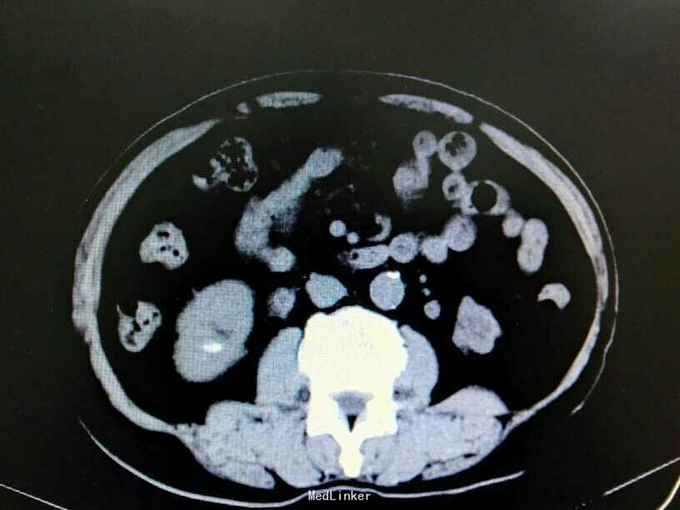

双肾铸型结石伴左肾萎缩一例

72岁男性,因“体检发现双肾结石1月”。既往10年前因双肾结石行双侧肾盂切开取石术(具体不详)。4年前因右肾输尿管结石行右侧输尿管碎石术。

双肾区叩痛。尿常规白细胞1500个/ul,两次尿培养阴性。左肾GFR15右侧38.9。

双肾铸型结石 左肾萎缩,尿路感染,双肾盂切开取石术后,BPH。经抗感染等治疗后,现在尿常规白细胞395.4个/ul。